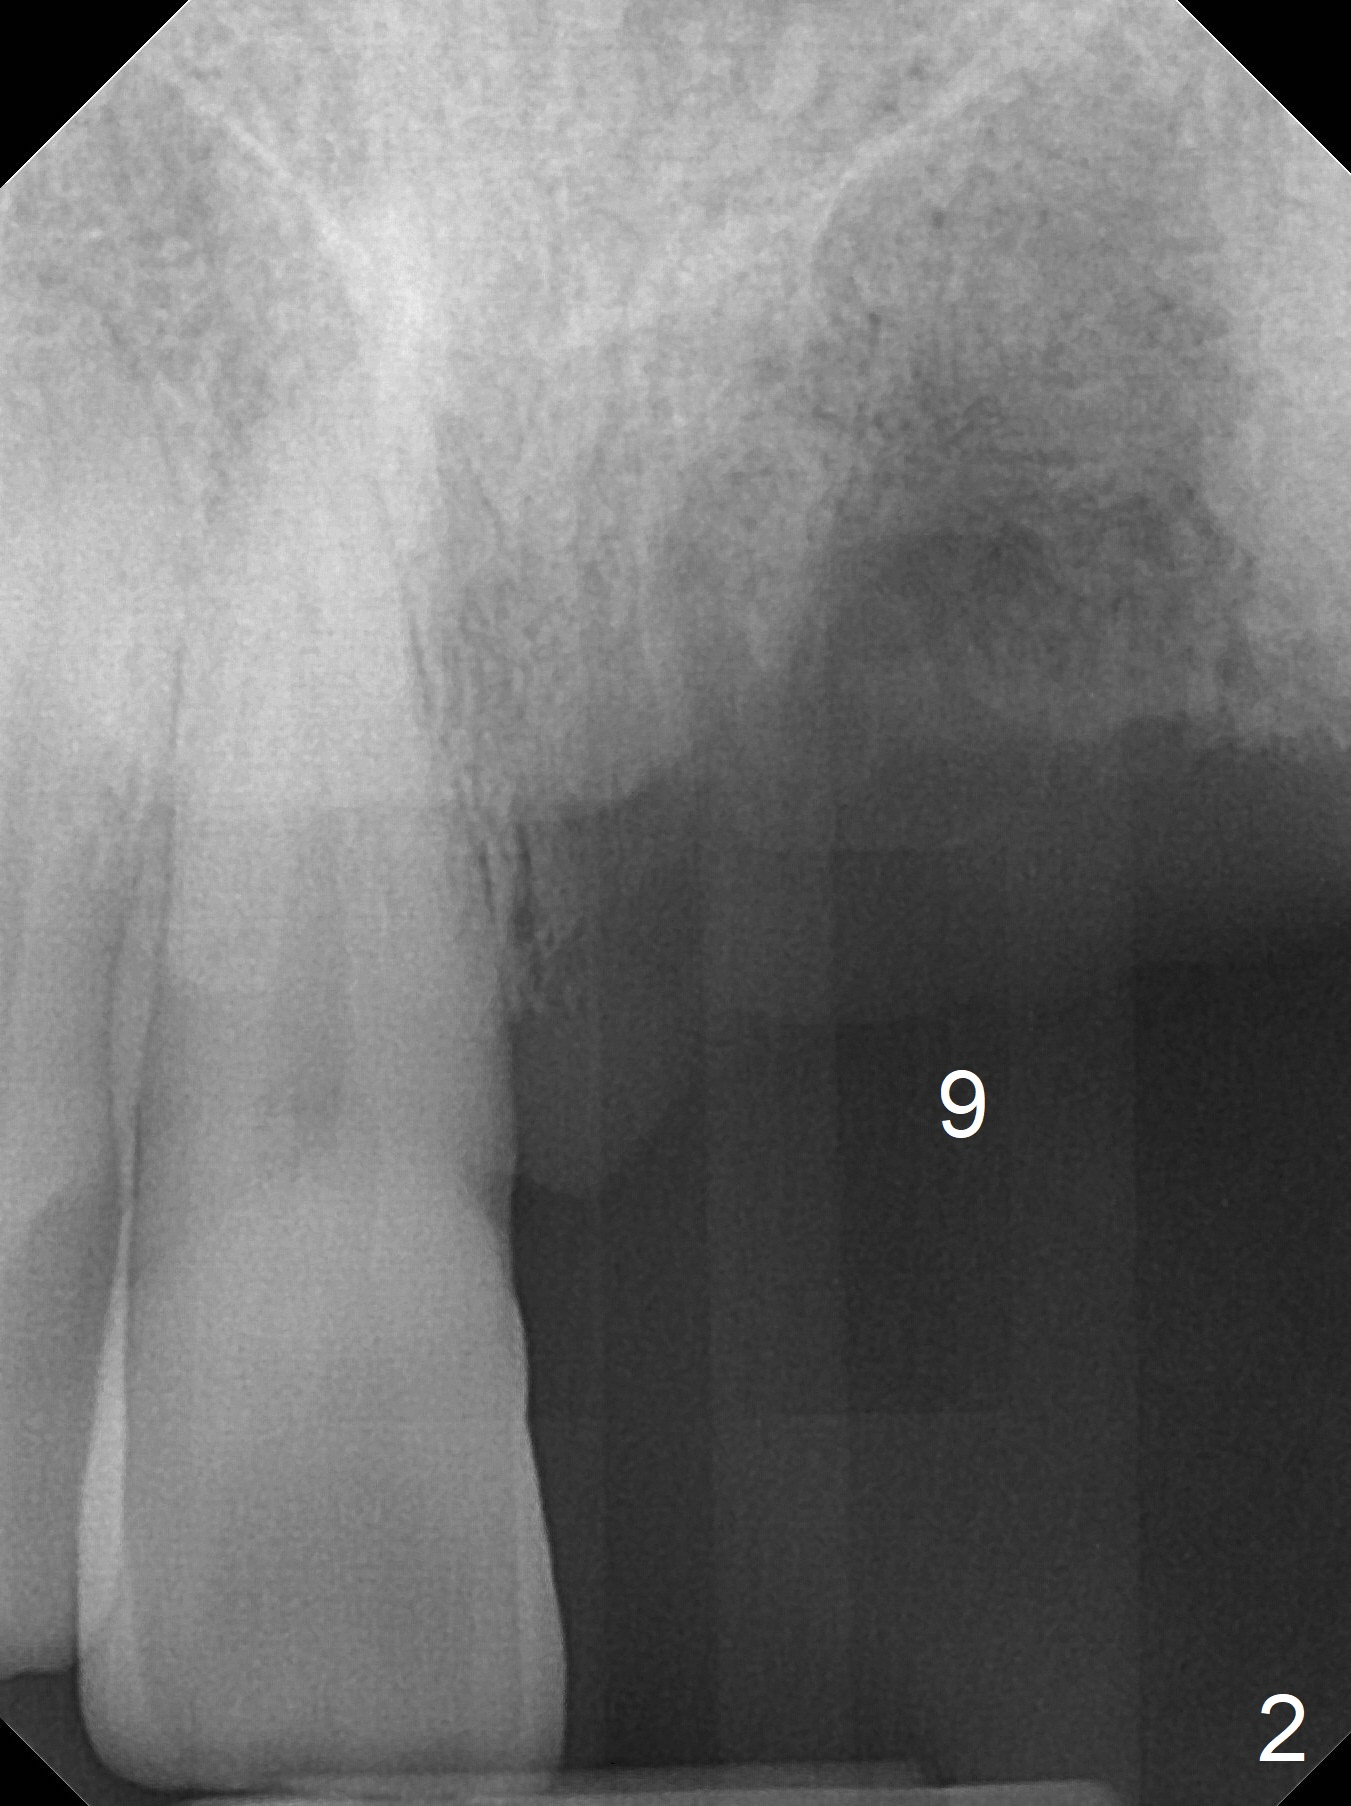

A 45-year-old man requests implant replacement for #5, 9 and 24-26 (Fig.1) after extraction of the tooth #9 (Fig.2). The teeth #24-26 have severe bone loss with mobility III (Fig.3). Since their roots are close to each other (Fig.4 (after extraction)), osteotomy will be initiated at #24 and 26 (Fig.5).